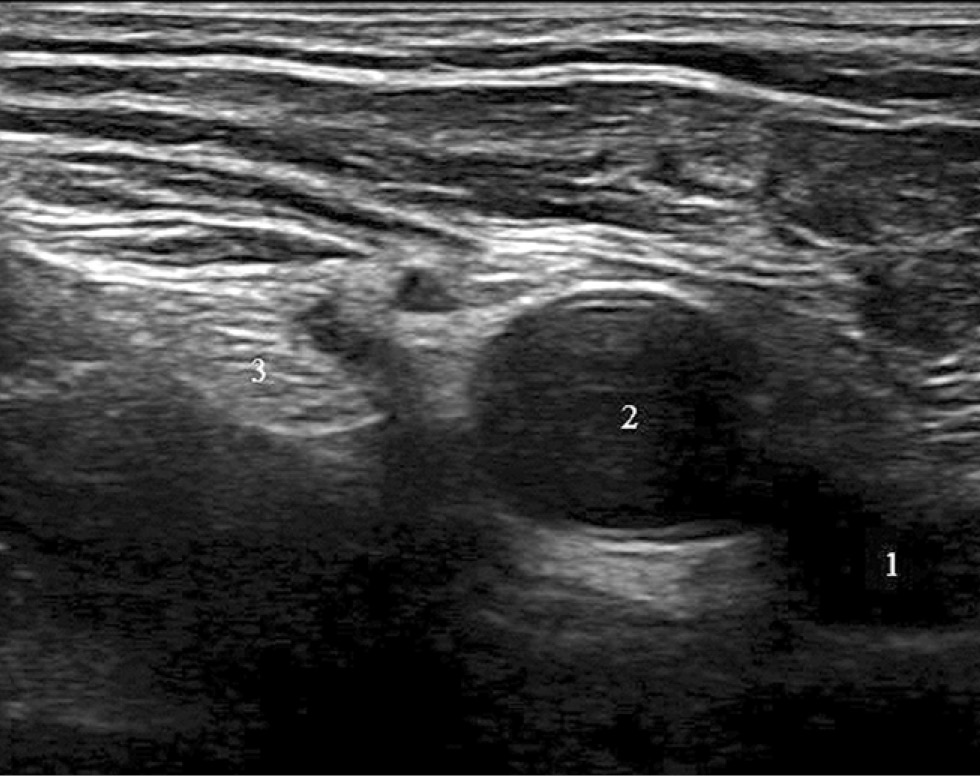

Fig. 1. Ultrasound image of the femoral nerve.

Note. 1 — femoral vein, 2 — femoral artery, 3 — femoral nerve.